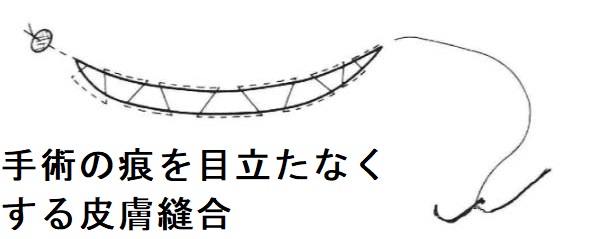

甲状腺手術の痕は、特に若い女性の場合、美容上の問題になります。

甲状腺手術の痕を目立たなくする皮膚縫合は形成外科の領域です。細い縫合糸、無傷針付きの形成外科用縫合糸を用いる様です。縫合法は、単一結節縫合、垂直マットレス縫合、埋没縫合、埋没連続縫合(仙台市立病院医学雑誌より)などです。

長崎甲状腺クリニック(大阪)が提携する大阪警察病院 内分泌外科では、甲状腺手術の皮膚縫合を形成外科がおこなうとの事です。

甲状腺内視鏡手術・甲状腺ロボット手術も傷口が小さくて済みます。しかし、大きな甲状腺腫・腫瘤、リンパ節転移・周囲浸潤の強い甲状腺癌には対応できません。

海外では、PRP(自己多血小板血漿)療法が試されています。甲状腺摘出術後の頸部創傷治癒促進と瘢痕形成抑制(血管増殖抑制、色素沈着の改善、柔軟性の向上)が目的[Cureus. 2025 Jun 5;17(6):e85404.]